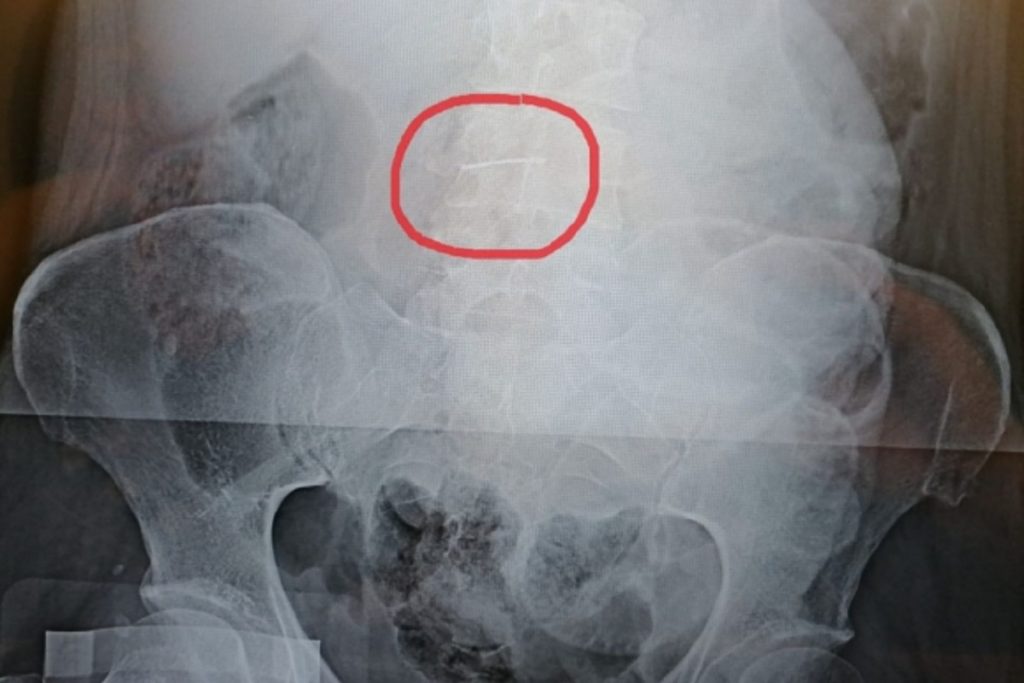

Как сообщает облздрав, пациентку по экстренным показаниям неотложкой доставили в больницу с подозрением на желудочно-кишечное кровотечение. Диагноз не подтвердился, однако рентген показал, что в брюшной полости больной есть швейная игла. Волгоградские хирурги приняли решение о немедленной операции.

Однако женщину удалось спасти. Врачи извлекли из ее живота иглу длиной 5 см. К счастью, острый предмет не успел повредить органы.

В 2004 году женщина работала на швейной фабрике, там получила случайную травму и игла попала в брюшную стенку. Затем предмет оказался в брюшной полости и застрял в сальнике.